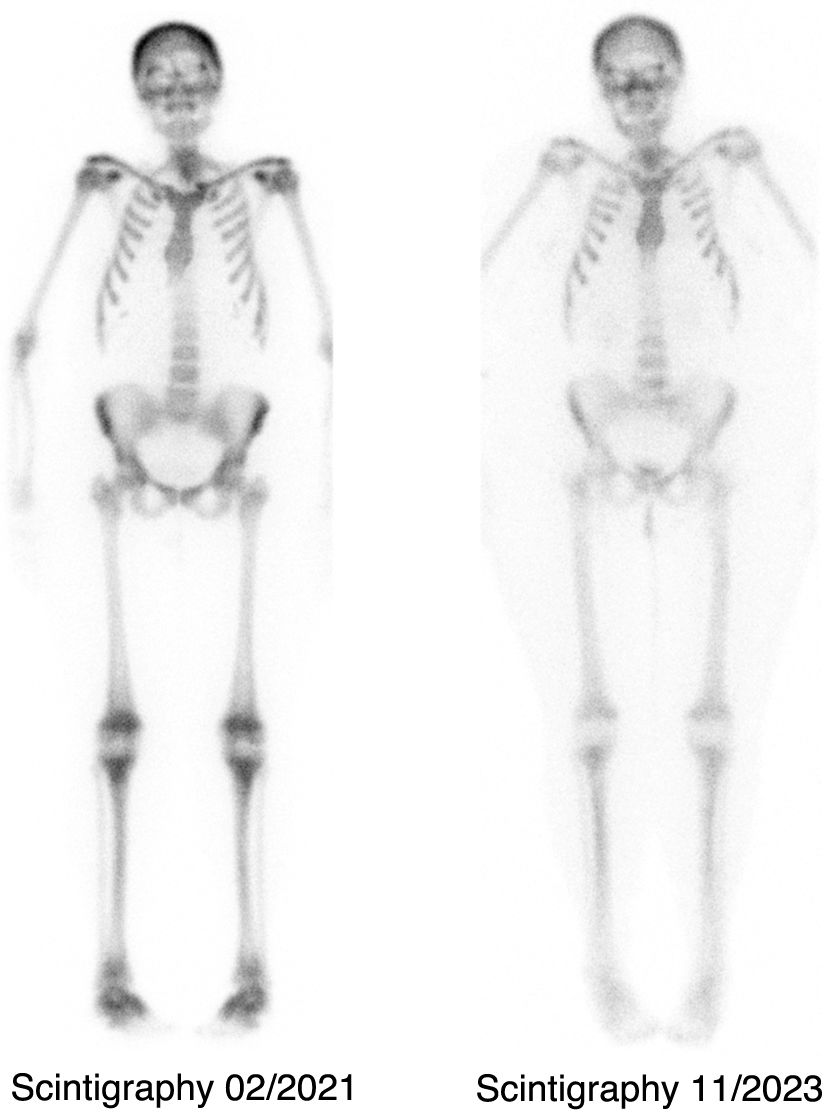

In March 2021, she was evaluated by rheumatology for diffuse polyarthralgia and lumbar pain of 2 months’ duration. Laboratory tests showed: albumin-corrected calcium 9.5 mg/dL, albumin 4.1 g/dL, magnesium 1.6 mg/dL, phosphate 4.4 mg/dL, alkaline phosphatase 149 U/L, 25-OH vitamin D 39.9 ng/mL, PTH < 6 pg/mL, calciuria 584 mg/24 h, phosphaturia 1035 mg/24 h, rheumatoid factor and anti-CCP negative, C-reactive protein 1 mg/L, ESR 10 mm/h. Radiography showed increased bone density and lytic lesions in the lumbar spine, shoulders, hips, and knees, all suggestive of hyperparathyroidism. Bone scintigraphy (99mTc-diphosphonates) demonstrated a metabolic “superscan” pattern with highest uptake in the calvaria, pelvis, and lower limbs (Fig. 1).

In September 2021, gastric bypass reversal was performed and teriparatide was discontinued. Thereafter, she experienced progressive improvement in axial/joint pain, decreased uptake on scintigraphy (Fig. 1), and stable calcium levels (11.4 mg/dL) with calciuria 182 mg/24 h. She has had no further episodes of tetany.

After nearly 4 years of teriparatide therapy, our patient developed clinical and radiographic features of hyperparathyroidism, despite suboptimal calcium control. Bone scintigraphy is not diagnostic but is useful for assessing skeletal involvement.13 In primary hyperparathyroidism, tracer uptake intensity appears to correlate with radiographic severity.11

To date, no cases have described long-term teriparatide therapy with joint symptoms, radiographic features of induced hyperparathyroidism (eg, “rugger-jersey spine”), and a “superscan” scintigraphic pattern, with progressive improvement following gastroileal bypass reversal.